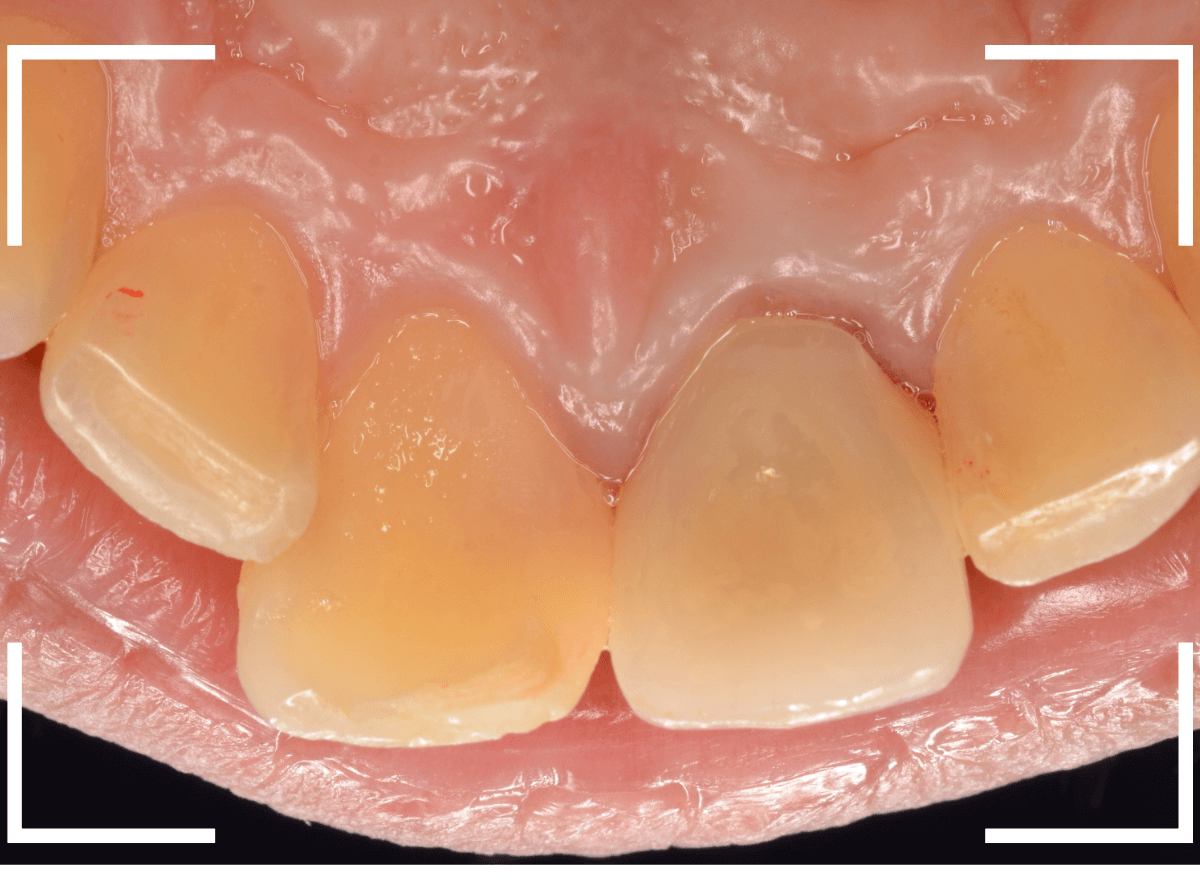

「レジン前装冠」は裏から撮影した写真を見ていただければわかるように、銀歯の上にレジン(プラスチック)を盛ったさし歯で、実質的には銀歯です。

銀歯の上にプラスチックを盛るために、歯をかなり大きく削る必要があったり、短期間で劣化・変色する(この方の差し歯も劣化してのっぺりした黄土色になっています)、金属の色素が歯肉に溶け出して歯肉が黒くなる(メタル・タトゥー)などのデメリットがあります。

虫歯を除去後に、裏側から撮影したところです。

思っていた以上に神経ギリギリ、歯全体に渡る大きな虫歯でした。

そのとなりの〇部の歯も同じように広くレジンをつめる治療をしてある中が大きな虫歯になっていました。